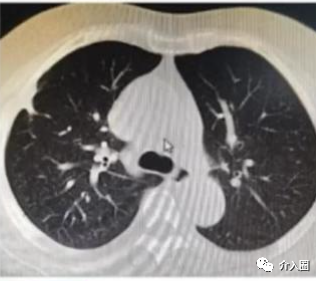

肺鱗癌應用實例(來源:康博刀官方資料)

患者信息:肺鱗癌患者,病灶侵犯胸壁引起疼痛

治療方案及過程:冷凍消融術中血壓高,靜脈泵入硝普納,配合舒緩音樂降壓

治療結果:術后6個月復查,同樣顯示條索樣改變

▲圖8 術前與術后